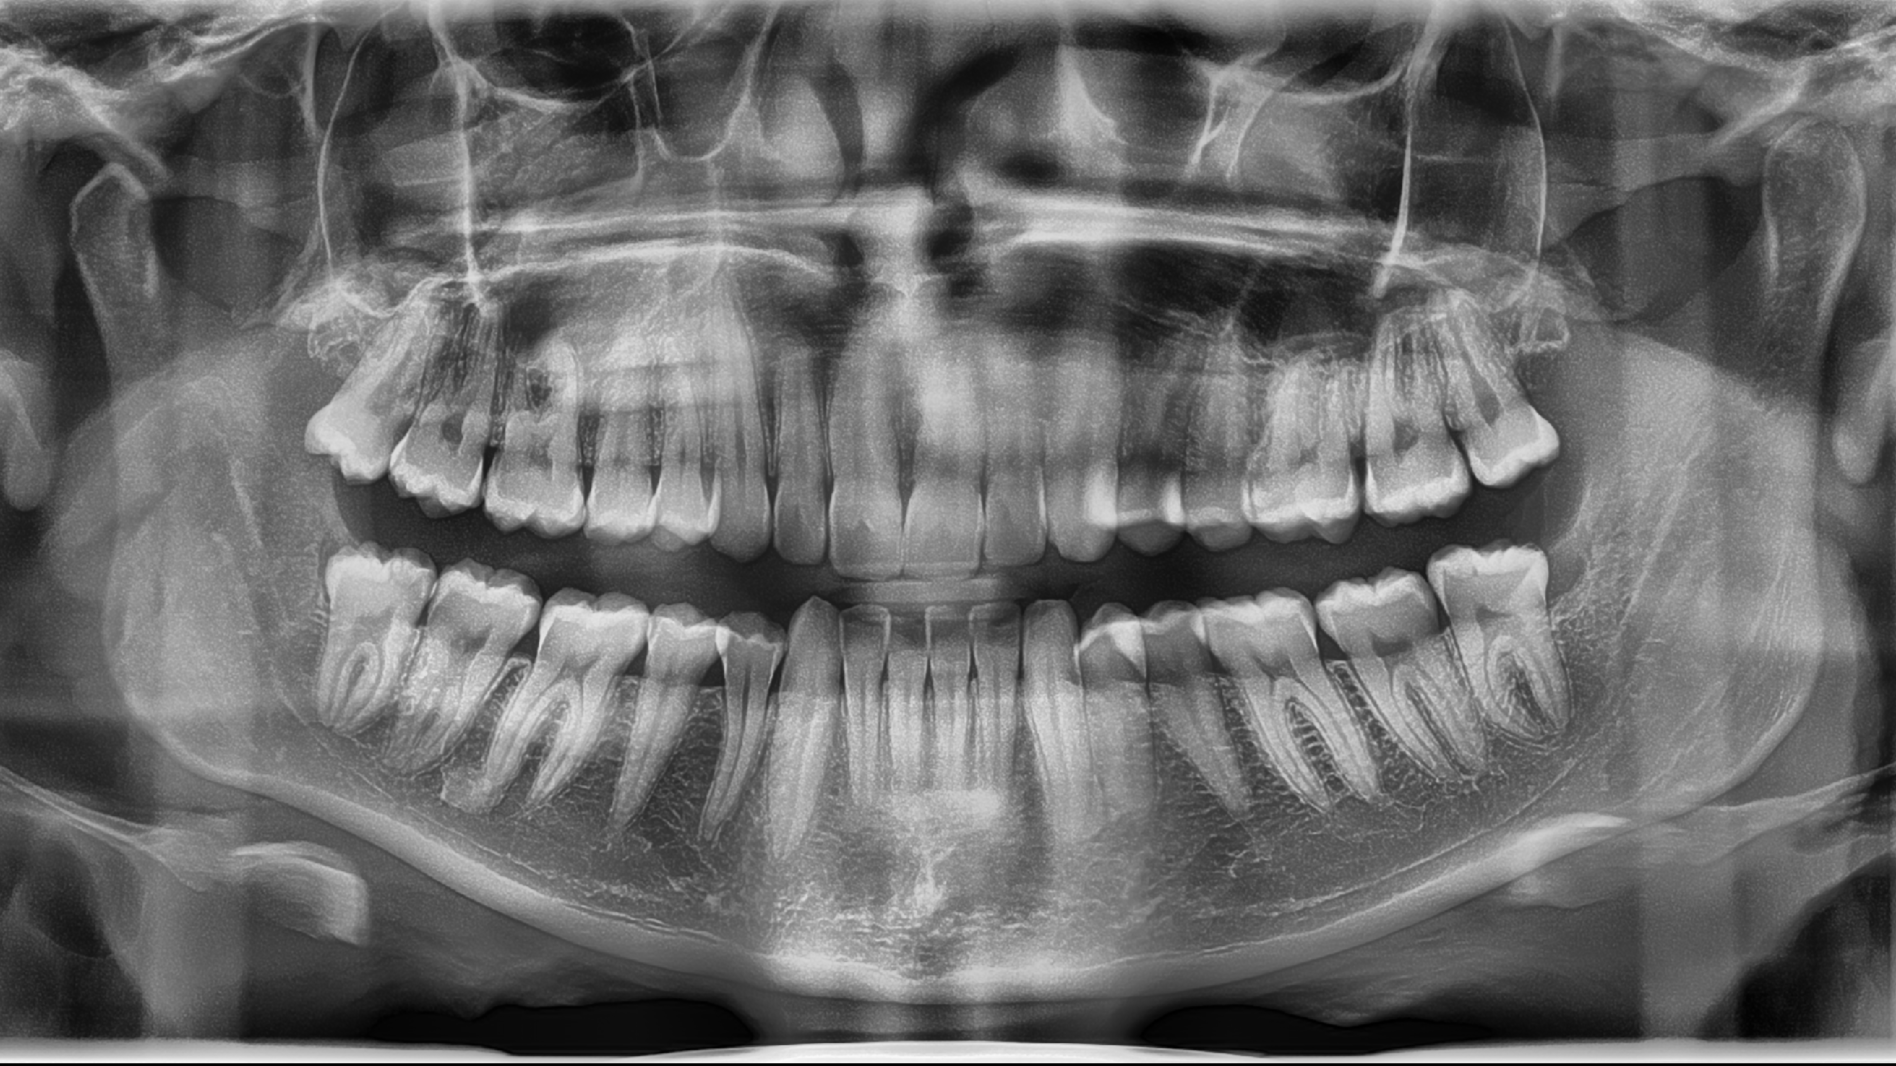

An OPG (Orthopantomogram) is a wide, panoramic dental X-ray that captures all the teeth, upper and lower jaws, and surrounding bone in a single image. It helps your dentist assess tooth position, wisdom teeth, jaw joints and overall oral health.